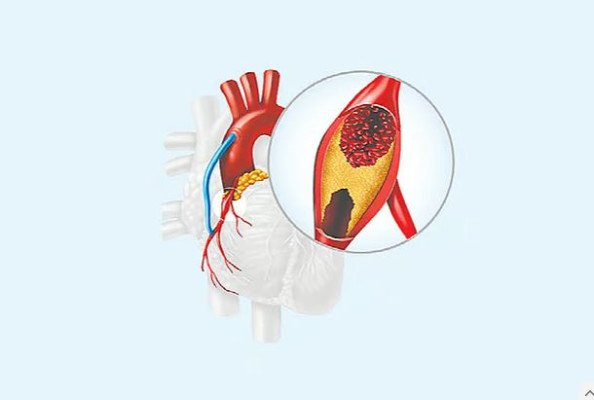

হার্টের রক্ত সরবরাহকারী প্রধান নালিগুলোর নাম করোনারি ধমনি। এই ধমনিগুলোতে ব্লক বা রক্ত চলাচলে বাধা সৃষ্টি হলেই করোনারি হৃদ্রোগ হয়। সাধারণত এক দিনে হঠাৎ করে কোনো করোনারি ধমনি সম্পূর্ণ ব্লক বা বন্ধ হয়ে যায় না। এটি দীর্ঘদিন ধরে ধীরে ধীরে গড়ে ওঠা একটি প্রক্রিয়া। ফলে রোগের শুরুর দিকে অনেক সময় কোনো স্পষ্ট উপসর্গ দেখা যায় না। যখন রক্তনালির ব্লক একটি সংকটজনক পর্যায়ে পৌঁছে, তখন হৃদ্পেশিতে রক্ত সরবরাহ ব্যাহত হয় এবং নানা উপসর্গ প্রকাশ পেতে শুরু করে।

করোনারি হৃদ্রোগের সবচেয়ে সাধারণ লক্ষণ হলো বুকে ব্যথা। এই ব্যথা সাধারণত বুকের মাঝখানে অনুভূত হয়। ভারী কাজ, সিঁড়ি ভাঙা, দ্রুত হাঁটা কিংবা দৌড়ানোর সময় এই ব্যথা বাড়তে পারে এবং বিশ্রাম নিলে কমে যায়। অনেক ক্ষেত্রে বুকে চাপ, ভারী ভাব বা অস্বস্তিও অনুভূত হয়। ব্যথা ছড়িয়ে পড়তে পারে ঘাড়, কাঁধ, চোয়াল, বাঁ হাত কিংবা পিঠের দিকে। যদি হঠাৎ করে তীব্র বুকে ব্যথা শুরু হয়, বিশ্রামেও না কমে, দীর্ঘ সময় স্থায়ী হয় এবং সঙ্গে ঘাম, বমি বা বমিভাব দেখা দেয়, তবে সেটি হার্ট অ্যাটাকের লক্ষণ হতে পারে। করোনারি ধমনি সম্পূর্ণ ব্লক হয়ে গেলে হার্ট অ্যাটাক হওয়ার ঘটনা ঘটে।